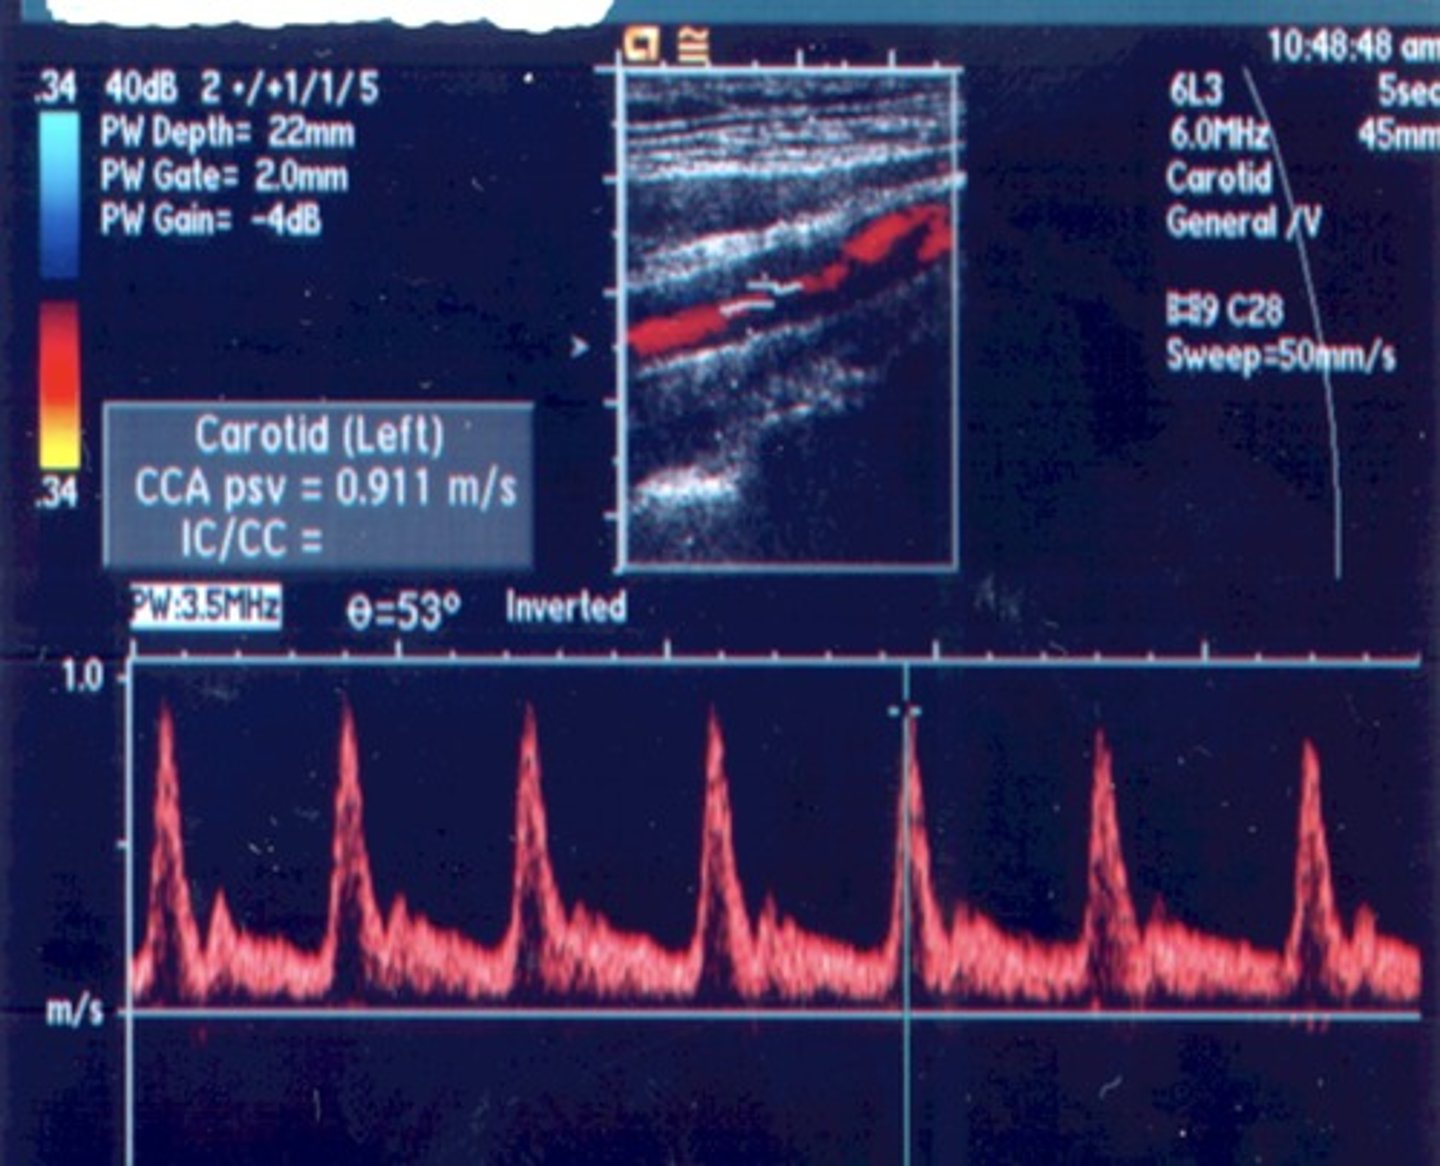

Normal Prox CCA Waveform

Normal CCA Waveform